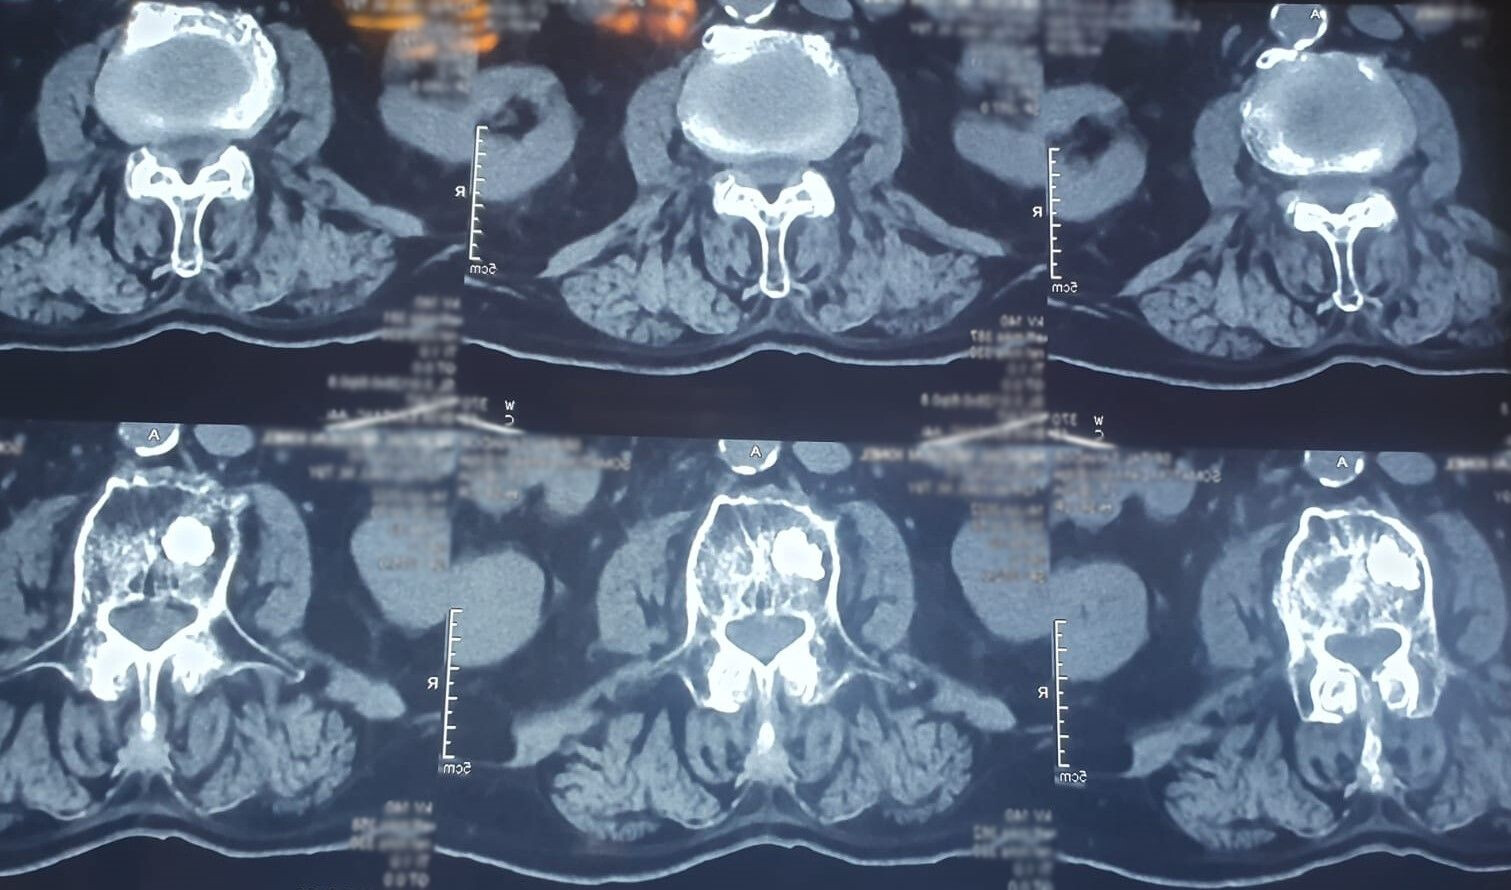

Cu astfel de dureri a venit Ionel la o consultație la Dr. Dan Benția, medic primar neurochirurgie la Spitalul Clinic SANADOR. Pacientului îi era imposibil să se deplaseze sau chiar să stea în picioare, din cauza durerilor de spate care nu treceau în niciun fel. În urma consultului și a investigațiilor realizate, Ionel a primit diagnosticul: tasări multiple pe os patologic tumoral la 5 niveluri. Astfel, s-a decis necesitatea intervenției chirurgicale, prin vertebroplastie percutanată.